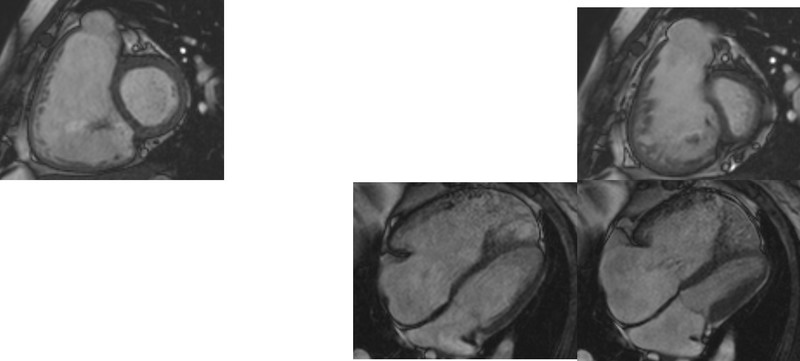

▲右上:右室が左室を圧排、右下・左上:右心系の拡大

こちらは肺高血圧症の心臓MRI画像です。心臓MRIは肺高血圧症で最も負担がかかる心臓の右心室の評価に適した検査で、左心室や右心室の容積や、心筋量などから両心機能と右室肥大の評価ができます。この症例画像からは右心室の拡大と肥大が確認できます。